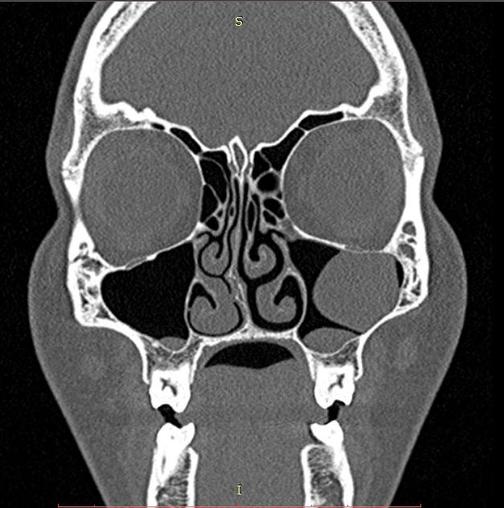

Киста В Голове Фото

Киста В Голове Фото 146 фотографий